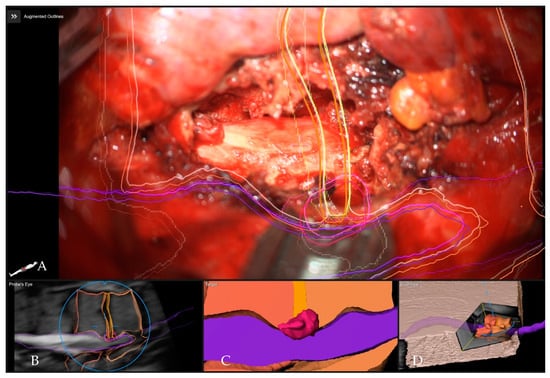

5.4. Applications of Augmented Reality for Degenerative Spine Surgery